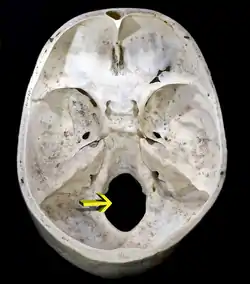

![]() Upper surface of base of the skull. The hole indicated by an arrow is the foramen magnum | |

The foramen magnum (Latin: great hole) is a large, oval-shaped opening in the occipital bone of the skull. It is one of the several oval or circular openings (foramina) in the base of the skull. The spinal cord, an extension of the medulla oblongata, passes through the foramen magnum as it exits the cranial cavity. Apart from the transmission of the medulla oblongata and its membranes, the foramen magnum transmits the vertebral arteries, the anterior and posterior spinal arteries, the tectorial membranes and alar ligaments. It also transmits the accessory nerve into the skull.

The foramen magnum is a large, oval-shaped opening (foramen) in the occipital bone of the skull.[2] It is present in humans, and in many other animals. Anteriorly, it is bounded by the basiocciput.[2] Posteriorly, it is bounded by the supraocciput.[2] Laterally, it is bounded by the occipital condyles.[2]